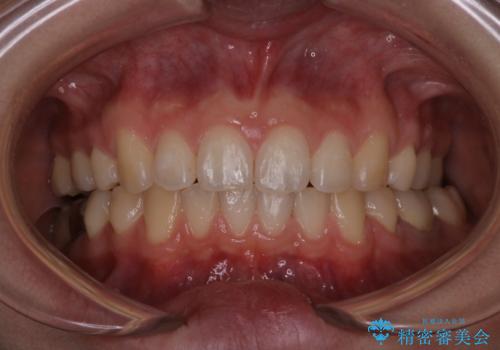

出っ歯の矯正 抜歯をしてしっかり引っ込めるワイヤー矯正

見た目もよくなり、口も閉じるようになったと満足していただけました。

予定よりも早く終了することができたことにも喜んでいただけました。